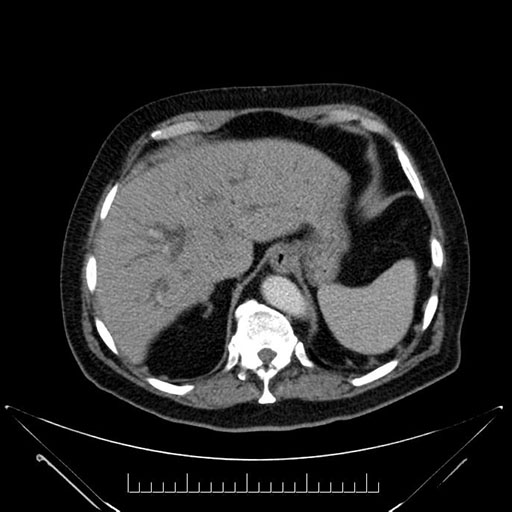

Imaging Analysis

Look through the patient's CT scan to identify any areas of concern for the necessary procedure.

Based on your CT findings, which issue(s) would give reason for "planned slowing down moment(s)" in this case?